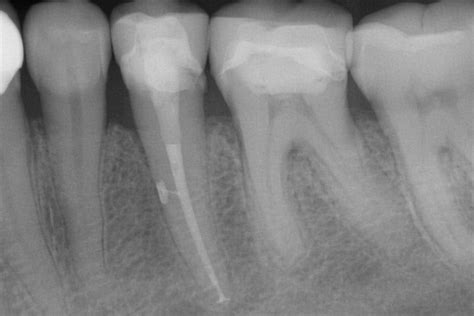

- Zusätzliche Wurzelkanäle: Viele Misserfolge bei Wurzelbehandlungen beruhen darauf, dass nicht alle Wurzelkanäle gefunden und gefüllt werden. Unbehandelte Wurzelkanäle können dann zu chronischen Entzündungen und Schmerzen führen.

Füllung der Wurzelkanäle

Die gereinigten, desinfizierten und getrockneten Wurzelkanäle werden nun bis zur Wurzelspitze möglichst dicht mit einer Wurzelfüllung verschlossen. Dazu wird ein dickflüssiger Zement (Sealer) und Stifte aus Guttapercha in den Kanal eingeführt. Die Guttapercha kann auch mit speziellen Instrumenten (Plugger) komprimiert werden (Kondensation) oder durch Hitze erweicht werden (thermoplastische Wurzelfüllung) um auch die Verästelungen der Wurzelkanäle (sogenannte Seitenkanäle) bestmöglich abzudichten.

Verschluss des Zahnes und Röntgenbild

Nach der Wurzelfüllung wird der Zahn von oben mit einer Kunststoff-Füllung (Komposit) bakteriendicht verschlossen. Der hermetische Verschluss ist sehr wichtig, da der Wurzelkanal ansonsten wieder durch Bakterien aus der Mundhöhle besiedelt wird. Eine Röntgen-Kontrollaufnahme dokumentiert am Ende die durchgeführte Wurzelfüllung.